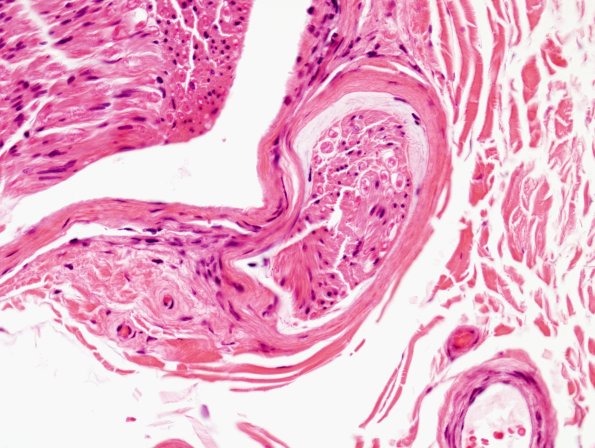

2A Edema, subperineurial (Case 2) H&E 1

Is this subperineurial edema or artifact? (H&E)